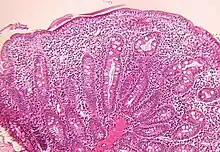

Small bowel

Microscopic examination of a biopsy of the small bowel in these patients shows villous atrophy with low or no mononuclear cell infiltration of the lamina propria nor specific abnormalities involving the epithelium. The amount of villous atrophy does not explain the severity of the diarrhea.

Studies of enterocyte brush-border ion transporter proteins (sodium-hydrogen exchanger 2, sodium-hydrogen exchanger 3, aquaporin 7, sodium iodide symporter and hydrogen potassium adenosine triphosphatase) showed reduced expression or mislocalization in all patients with different profiles for each.[6]